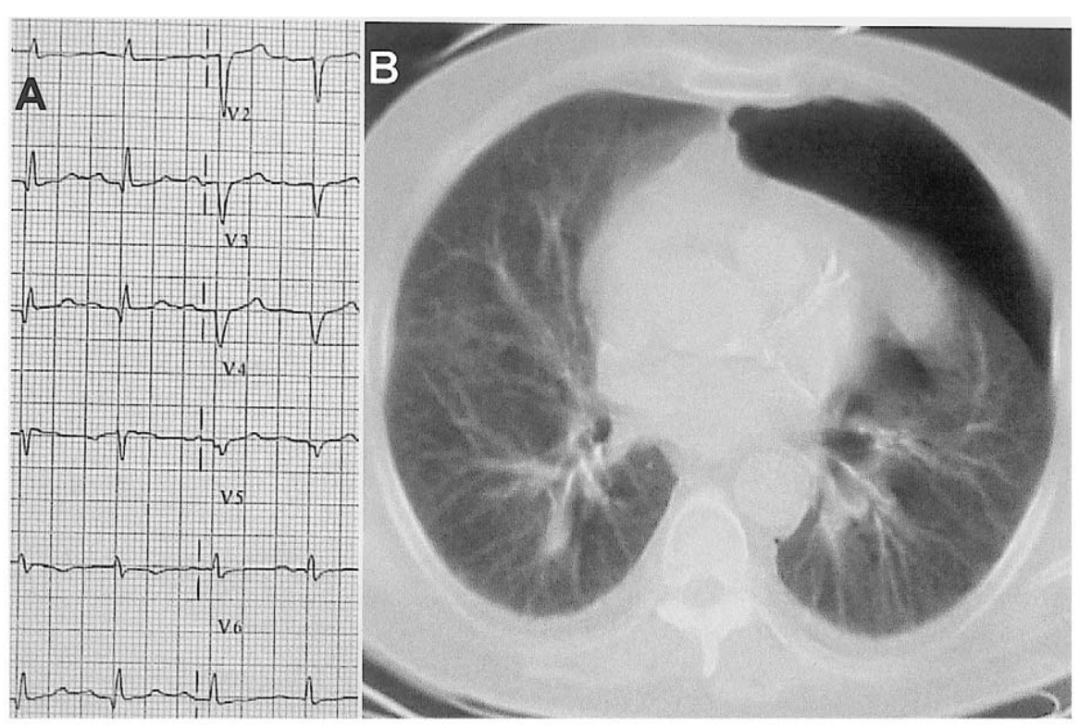

十二导联心电图(图8)显示v1–v4导联qrs低电压和qs形(a),与胸部ct扫描